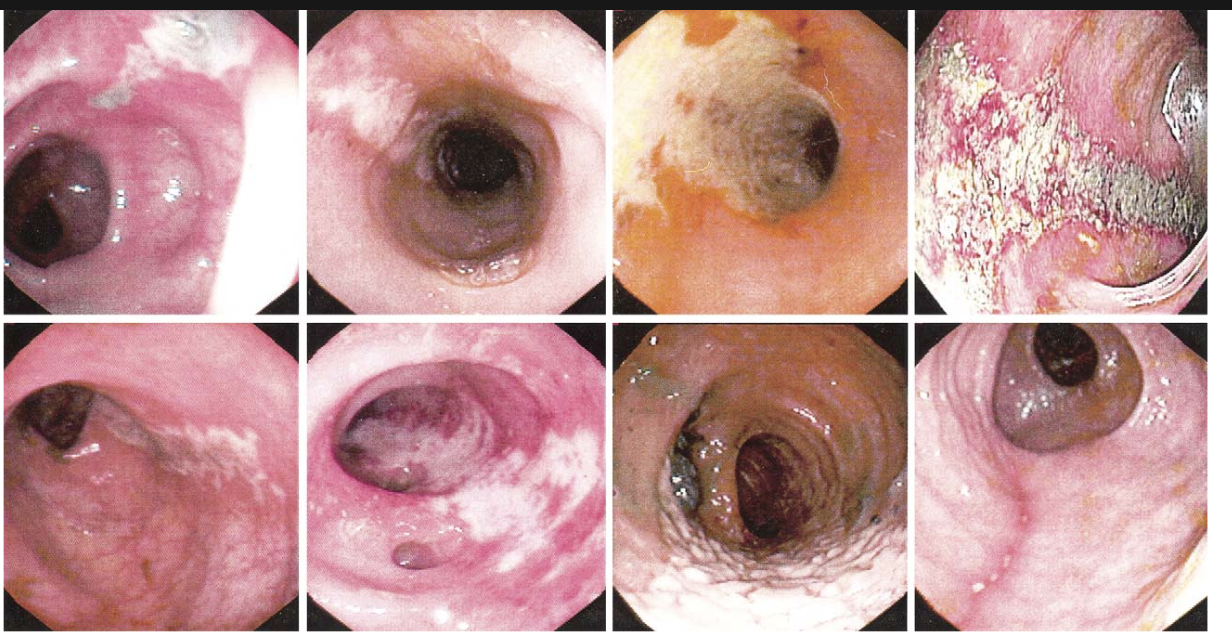

Single stripe sign of ischemic colitis